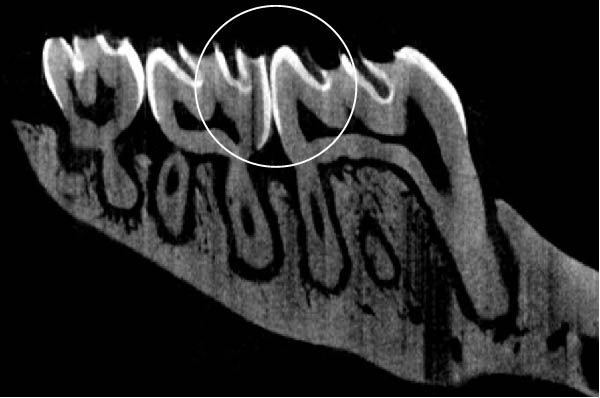

Figure 3 shows the micro‐CT images of OTM in some subgroups.

Figure 3Micro‐CT analysis of OTM after 21 and 40 days: (A) orthodontic treatment/CE injection/stress (chronic); (B) orthodontic treatment/CE injection/stress (acute); (C) orthodontic treatment/stress (chronic); (D) orthodontic treatment/stress (acute); (E) no orthodontic treatment/CE injection/stress (chronic); (F) no orthodontic treatment/CE injection/stress (acute); (G) no orthodontic treatment/no drug (chronic); (H) no orthodontic treatment/no drug (acute).(A)(B)(C)(D)(E)(F)(G)(H)